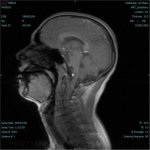

Schädel

seitlich

T2-gewichtetes

MRT |